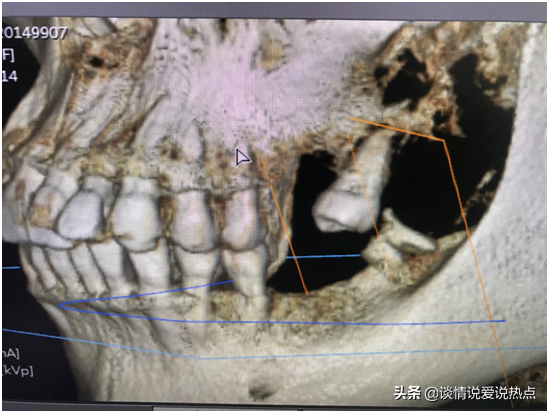

下圖是我現(xiàn)在左邊的牙齒,下頜有一顆殘根,要拔掉,上頜由于缺牙太久,旁邊那顆已經(jīng)歪得很嚴(yán)重,看到它歪成這樣我自己都被嚇到。從遠(yuǎn)期果考慮,醫(yī)生建議拔掉再種,不然下頜種上了兩顆,與這顆的咬合關(guān)系是擁擠的,咀嚼不力,咬合關(guān)系不好,長期使用就會受影響。加上這顆牙齒有齲壞,經(jīng)過深入的考慮,我還是決定拔掉種了。